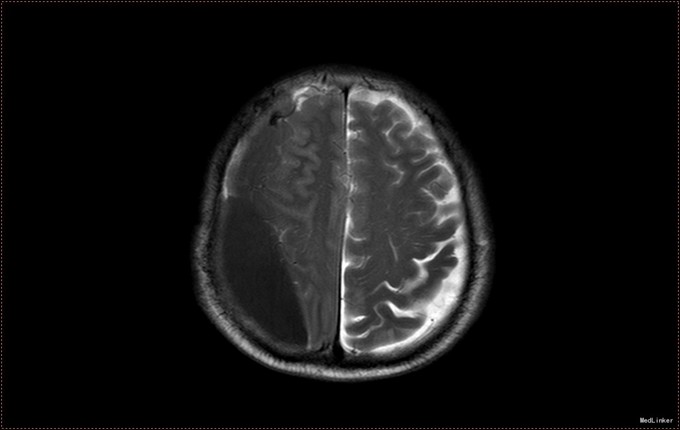

患者,男,53岁。以“左侧肢体疼痛伴无力1周”为主诉入院。患者1周前无明显诱因出现左侧肢体无力,伴酸痛,头部闷胀感,症状持续不缓解,于我院就诊,行头部CT及MR提示右侧顶枕叶硬膜下血肿。右侧额颞叶蛛网膜囊肿。患者为求进一步治疗,急诊以“硬膜下血肿”为诊断,收入病房。患者病来精神状态差,饮食睡眠可,二便可,体重无明显变化。否认近期头部外伤史。

入院查体:T:36.5℃ ,P:68次/分 ,BP:130/80mmHg , R:16次/分。步入病房,自主体位。神清语明,问答准确,查体合作,精神状态良好,定向力完整。粗测视野正常,双侧瞳孔等大正圆,D≈3.0mm,双侧眼球活动自如,对光反射灵敏。四肢活动自如,左侧肢体肌力V-级,右侧肢体肌力Ⅴ级,肌张力正常。深浅感觉检查未见异常。头CT及MR提示右侧颞极蛛网膜囊肿,右侧亚急性硬膜下血肿

患者诊断明确,完善术前检查行局麻右侧钻孔冲洗引流术,予常规治疗。术后3天拔管,复查头CT硬膜下血肿消失,但脑组织膨胀不良。患者左侧肢体肌力恢复正常,无头晕头沉症状,顺利出院。